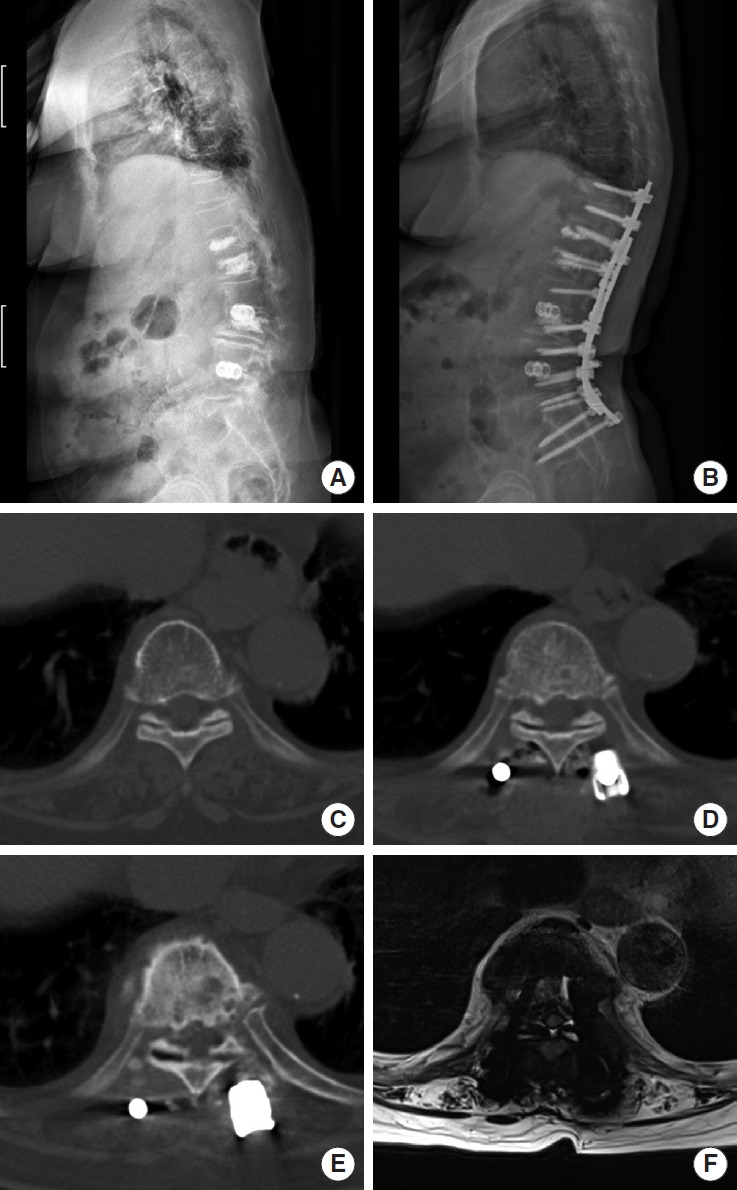

Abstract Image